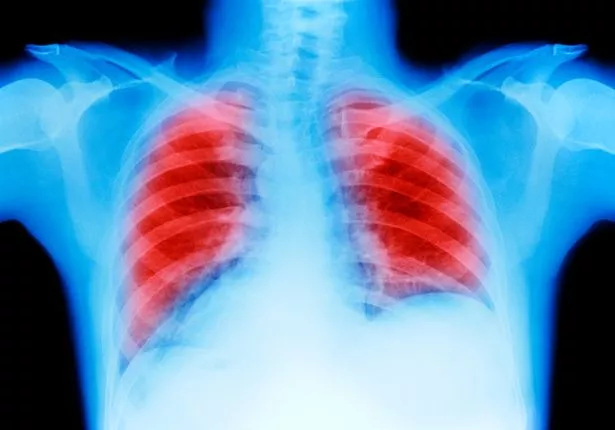

英国国家医疗服务体系表示:“肺癌是最常见、最严重的癌症之一。在英国,每年有超过4.3万人被诊断出患有这种疾病。”

医生将能够评估你的症状并进行诊断癌症所需的检查(图片:盖蒂)